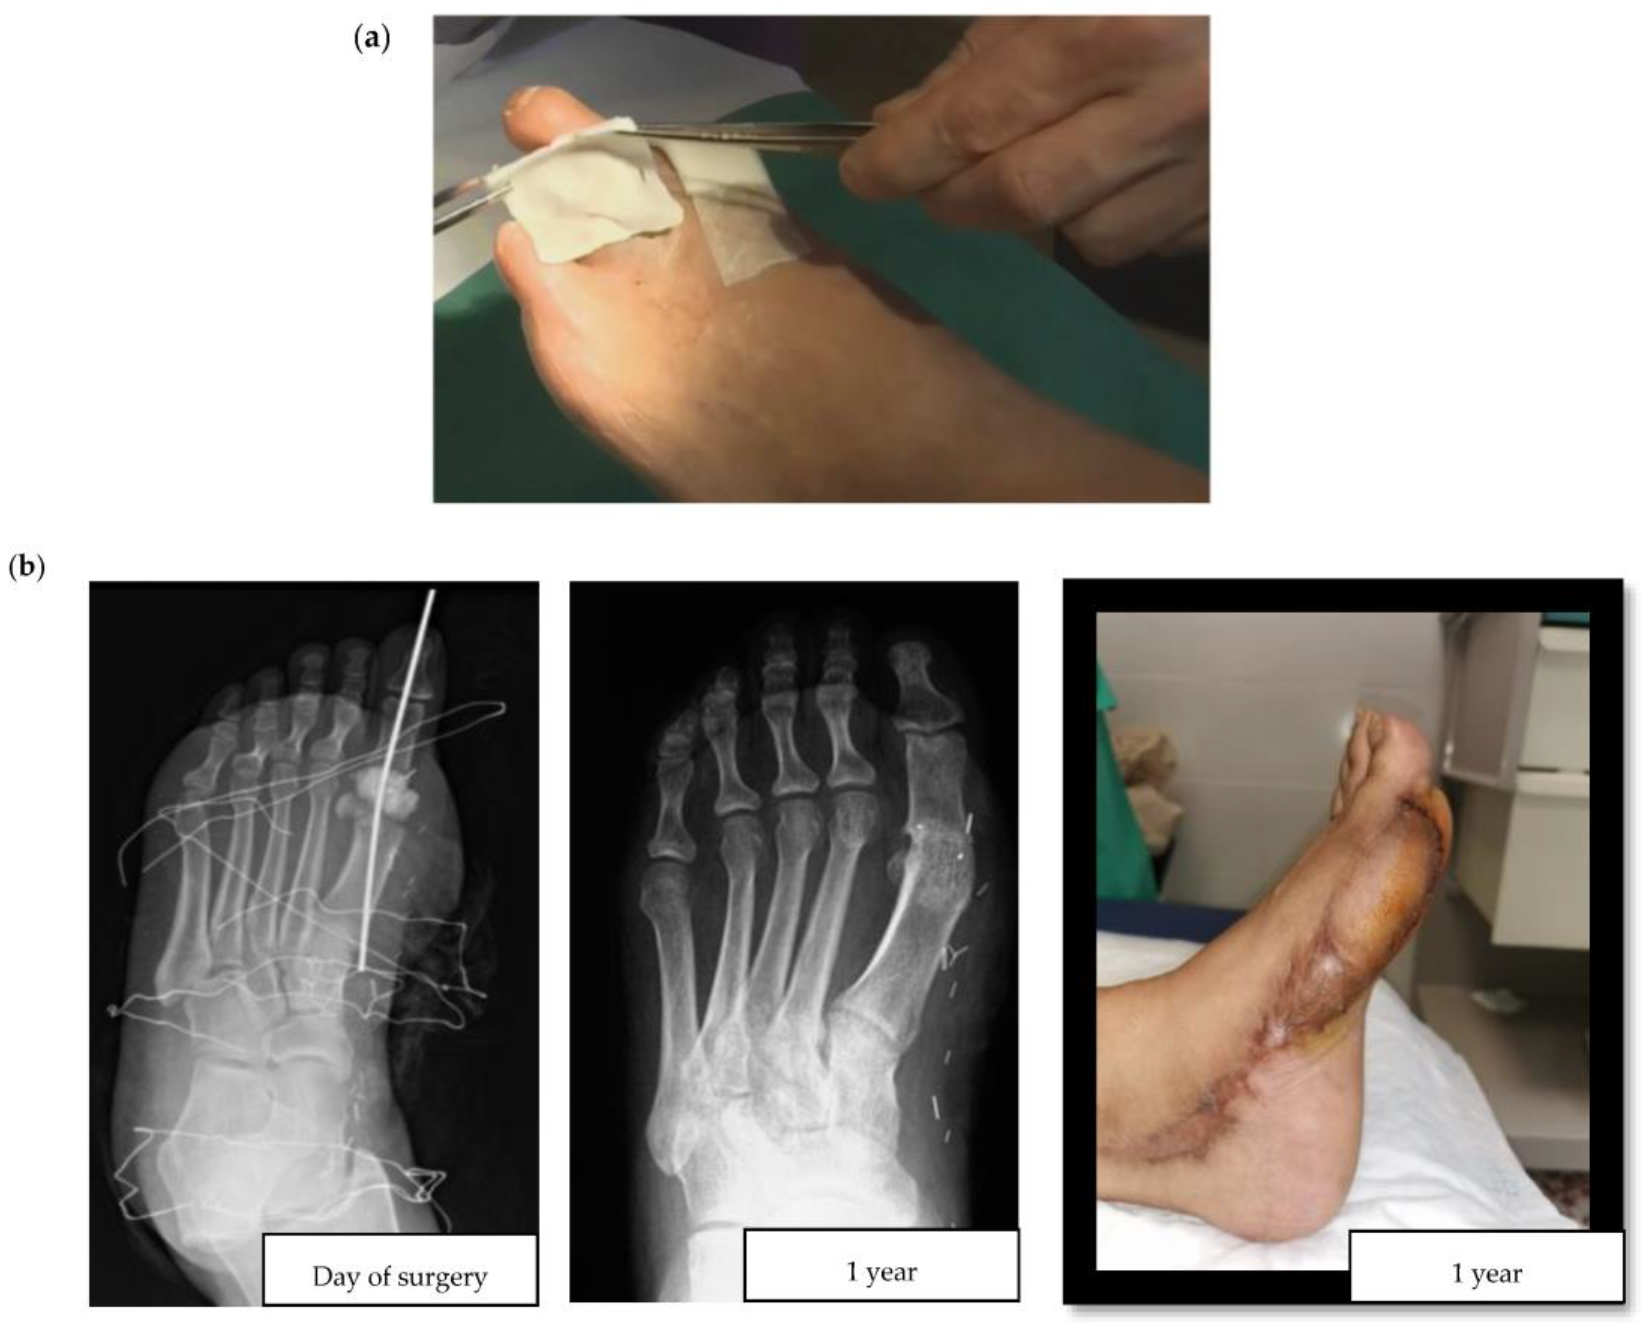

Researchers consistently apply the term topical to refer to the local administration of antibiotics through an infected diabetic foot ulcer (DFU). Topical antibiotic interventions have previously been studied in the assessment of the bioburden and biofilm of diabetic foot wounds [10]. For example, an in vitro experiment compared the efficacy of topical vancomycin and gentamicin to systemic antibiotics for the eradication of polymicrobial biofilms. The authors observed a bioburden reduction of 5 and 8 logarithms (colony forming units per milliliter), a finding with uncertain yet promising clinical relevance, and supportive of further studies to reveal the usefulness of topical antibiotic strategies in the surgical treatment of DFIs [11]. When considering the multiple topical antimicrobials available, it is also worth highlighting that a recent high-quality systematic review failed to show the superiority of any particular topical antimicrobial [12]. This lack of superiority could be partially explained by the local agent choices, encompassing a wide range of antiseptics, antibiotics, and antimicrobial dressings. More consistency in design is seen in clinical studies of local agents in DFIs since the gentamicin collagen sponge and the superficial pexiganan peptide (Figure 1a) tend to be incorporated.

Figure 1. (a) Application of a collagen sponge on a diabetic foot wound (courtesy of Dr. Ilker Uçkay); (b) Clinical case of a hallux valgus osteomyelitis with bone resection, filling with Cerament G® and a flap.

There are two major challenges associated with DFO surgeries: postoperative wound healing in the operated, and ischemia triggered by the residual death space of the former bone. In DFO treatment, two main types of antibiotic delivery system materials are currently available: non-absorbable and absorbable. According to the explored literature, the most frequently used non-absorbable material in DFO is polymethylmethacrylate (PMMA)—an acrylic used extensively in orthopedic surgery for chronic osteomyelitis and implant-related infections [18][19]. Some of the most common antibiotic-loaded commercial PMMA cements include Cemex®, Simplex®, Eurofix®, Palacos®, Copal®, and Refobacin®. As with all non-absorbable materials, the main disadvantage of PMMA is its surgical removal, resulting in additional intervention following the release of all drugs. Alternatively, there are hybrids of biodegradable carrier systems that take advantage of different properties to improve local antibiotic release. They have different presentations, such as Cerament G/V® (see Figure 1b for a clinical case example) or Stimulan® [20]. The development and use of contemporary absorbable biomaterials is an area of ongoing advancement. These materials have some advantages compared to PMMA, including better osteointegration and the lack of need for surgical removal. In this respect, the importance of considering the composition of these materials should also be highlighted, especially as to whether or not they contain hydroxyapatite, which is highly osteoconductive and promotes bone ingrowth. For example, the unique ratio of hydroxyapatite and calcium sulphate in Cerament® makes it particularly suitable for absorption and stimulation of new bone formation at the same rate. In contrast, Stimulan® only contains hemihydrate calcium sulfate, which retains its absorbable properties, but sacrifices osteoconductivity and bone growth.